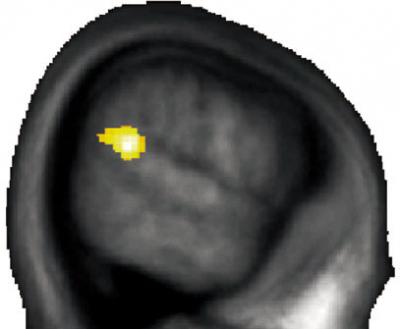

The volume of a small brain region influences one's predisposition for altruistic behavior. Researchers from the University of Zurich show that people who behave more altruistically than others have more gray matter at the junction between the parietal and temporal lobe, thus showing for the first time that there is a connection between brain anatomy, brain activity and altruistic behavior.

The aim of the study, however, was to find out why there are such differences. Previous studies had shown that a certain region of the brain – the place where the parietal and temporal lobes meet – is linked to the ability to put oneself in someone else's shoes in order to understand their thoughts and feelings. Altruism is probably closely related to this ability. Consequently, the researchers suspected that individual differences in this part of the brain might be linked to differences in altruistic behavior. And, according to Yosuke Morishima, a postdoctoral researcher at the Department of Economics at the University of Zurich, they were right: "People who behaved more altruistically also had a higher proportion of gray matter at the junction between the parietal and temporal lobes."

The participants in the study also displayed marked differences in brain activity while they were deciding how to split up the money. In the case of selfish people, the small brain region behind the ear is already active when the cost of altruistic behavior is very low. In altruistic people, however, this brain region only becomes more active when the cost is very high. The brain region is thus activated especially strongly when people reach the limits of their willingness to behave altruistically. The reason, the researchers suspect, is that this is when there is the greatest need to overcome man's natural self-centeredness by activating this brain region.